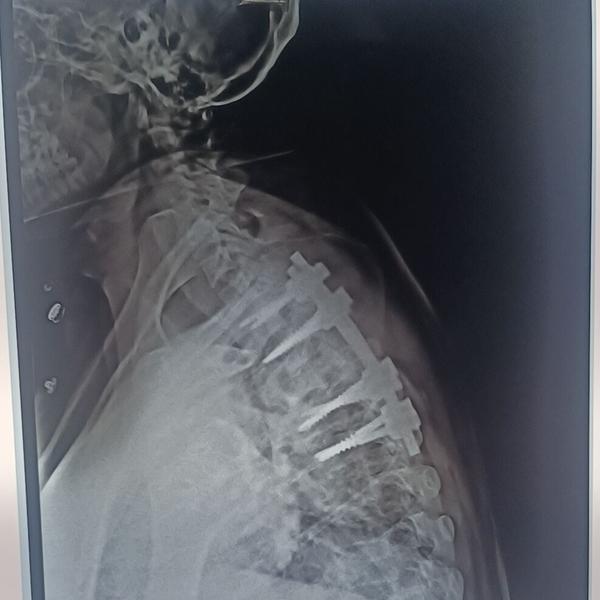

Best Spine Surgeon in Pune Best Spine Specialist in Pune Dr. Nitish Agarwal

View Details